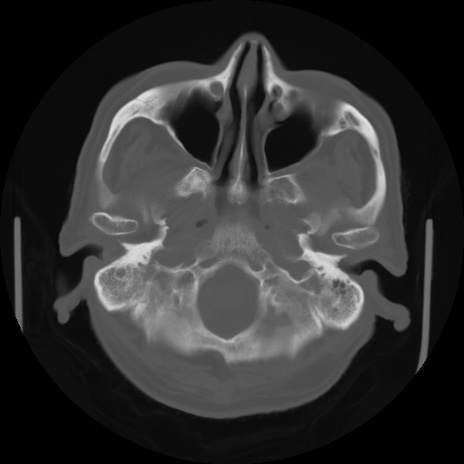

【頭部】症例5 CT(横断像)

【症例】80歳代 男性

【主訴】頭部打撲

【現病歴】外出先で椅子から立ち上がる際に、つまづいて後方へ転倒し受傷。転倒時に意識はあった。

【既往歴】高血圧、不整脈、アルツハイマー病

【身体所見】BP 217/71、HR 96、JCS1-1、 難聴あり、顔色良好、右後頭部に擦過創あり。神経学的異常なし。

症例5の画像所見と診断は?